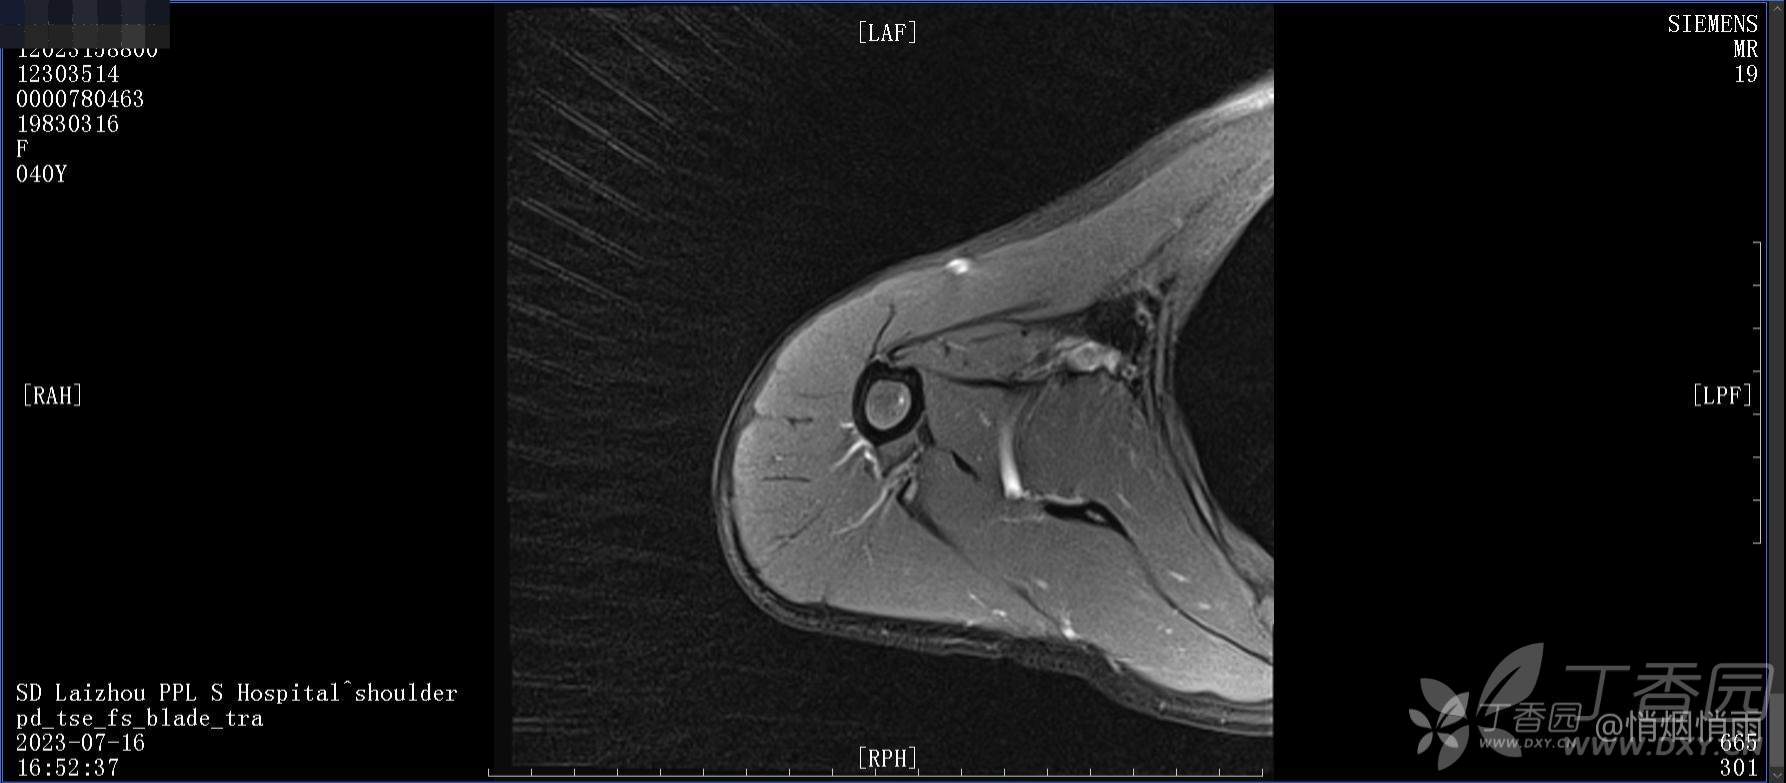

查体:右肩关节局部轻度肿胀,肩胛区压痛明显,痛处不固定,肩关节痛性活动受限,jobe test(+),lift -off test(+),中指、环指感觉较余指减退,余肢端感觉及血运情况可。

目前的诊断,暂时依据辅助检查诊为肩袖损伤,但是患者疼痛的性质和特点,却不是单纯的肩袖损伤所致。考虑过胸廓出口综合征,但是该疾病会出现肩胛区的疼痛吗?(由于考虑到费用的问题,没再进行下一步的检查)带状疱疹会有如此的症状吗?